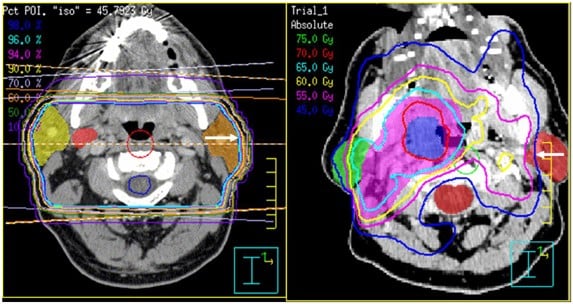

IMRT is a highly precise form of radiotherapy that allows doctors to control the intensity and direction of radiation beams with millimeter accuracy. Using advanced computer software, radiation doses are shaped to match the tumor's exact size and contour, reducing exposure to surrounding healthy tissues.

- Dose Mapping and Planning: Using 3D treatment-planning software, radiation specialists define target zones and safety margins around nearby organs. Multiple beam angles and intensities are calculated to ensure the highest dose reaches the tumor while sparing healthy tissues.